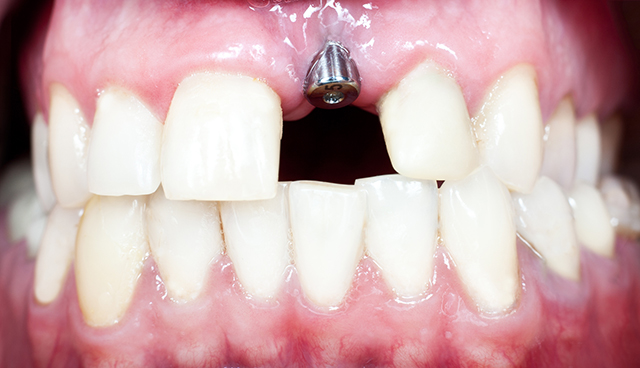

インプラント治療について

インプラント治療は、入れ歯のような異物感が無いうえに、ブリッジの様に支えとなる歯を削ることがありません。歯を失った方に現在提供のできる最良の治療法です。

歯を失った場合、入れ歯・ブリッジ・インプラントの3つの対応方法があります。インプラントは噛み心地が天然歯に近いメリットを持つ治療方法です。

インプラントはチタン製の人工歯根をあごの骨に直接埋め込むので、あごの力を直に伝えること・ズレないことなどから、固いものや弾力性があるものも食べることができます。

ブリッジは周囲の歯を削る必要がありますし、入れ歯は他の歯に金具を掛けますが、インプラントは周囲の歯に負担を掛けません。